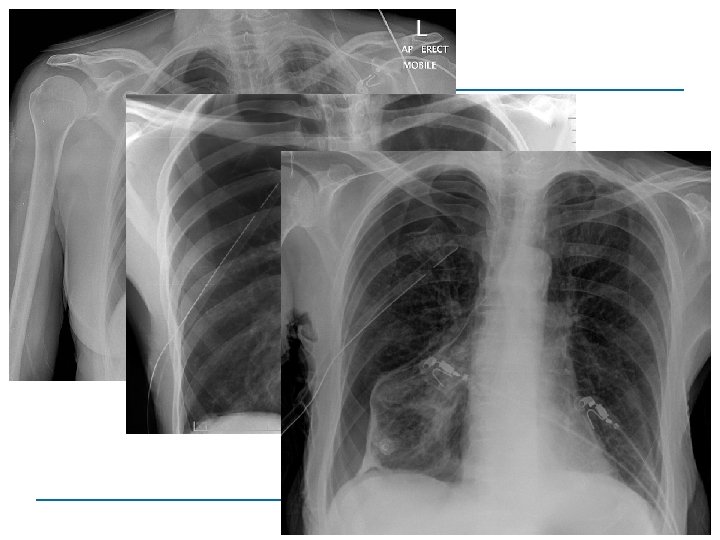

B Beatmung (B= Breathing and ventilation) Ziel: O 2 dorthin wo er gebraucht wird = Optimierung Gasaustausch Ursachen für Ventilationsstörungen Perikardtamponade Spannungspneumothorax Pneumothorax Hämatothorax Lungenkontusion Bronchusverletzungen Zwerchfellruptur

Spannungspneumothorax abgeschwächtes Atemgeräusch hypersonorer Klopfschall gestaute Halsvenen Kreislaufinstabilität (Mediastinalverlagerung) = SCHOCK Notfall-Dekompression Thoraxdrainage

Identifikation signifikanter Blutungen • klinische Untersuchung • • Röntgen Thorax • Sonographie Abdomen • Röntgen Becken